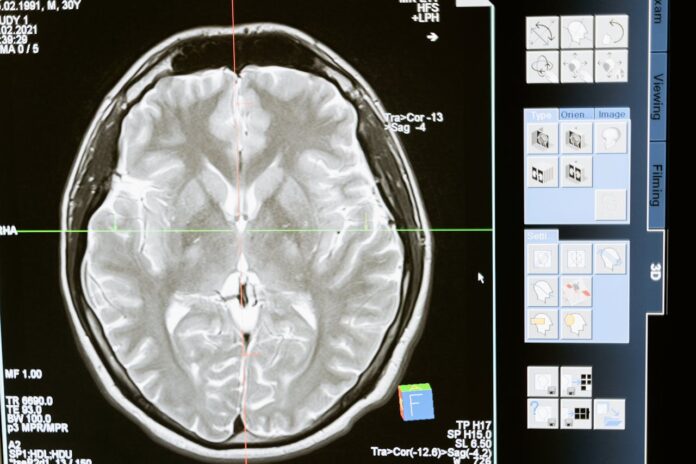

Badanie zostało przeprowadzone na 1441 dorosłych osobach w średnim wieku, uczestnikach koreańskiego badania społecznościowego. Wszyscy zostali poddani domowej polisomnografii oraz rezonansowi magnetycznemu (MRI) mózgu na początku badania (2011–2014), a następnie dwukrotnie w kolejnych latach (2015–2018 i 2019–2022). Dane analizowano między marcem 2024 r. a styczniem 2025 r. W grupie badawczej:

CMB definiowano jako dobrze zdefiniowane zmiany o średnicy <10 mm, o bardzo niskiej intensywności sygnału na obrazach T2*.